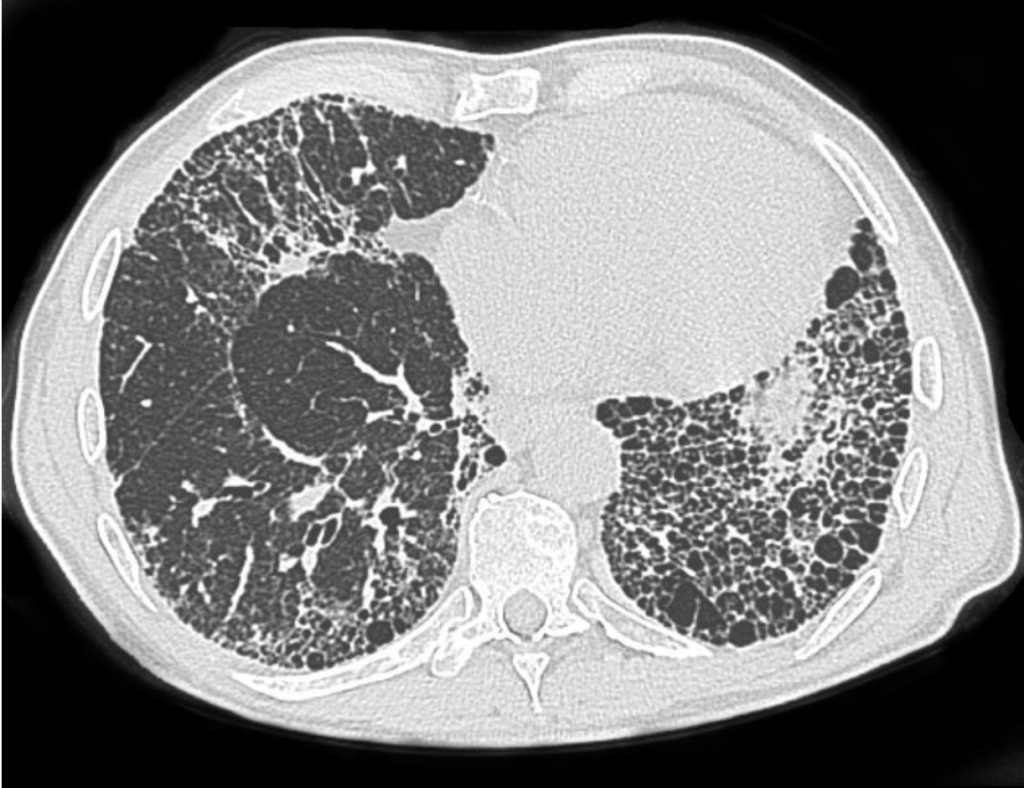

| Modality | Findings |

|---|---|

| CXR | Basal reticular/nodular opacities, pleural plaques, “shaggy heart” sign |

| HRCT | Subpleural linear opacities, parenchymal bands, honeycombing, plaques |